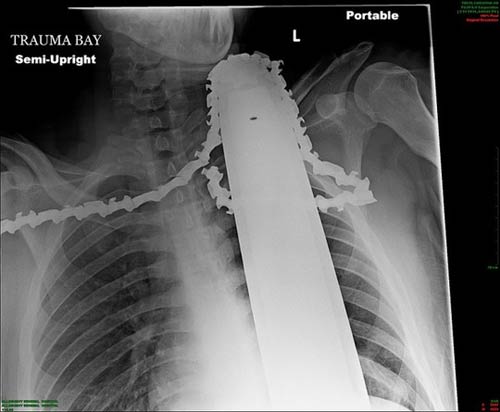

Phim chụp X-quang cho thấy chiếc cưa vướng bên trong cổ và vai của James Valentine, 21 tuổi. James tham gia chặt tỉa cây ở Pittsburgh, bang Pennsylvania – Mỹ và chiếc cưa máy bị trục trặc, bắn ngược vào trong người anh.

Chiếc cưa vướng bên trong cổ và vai của James Valentine